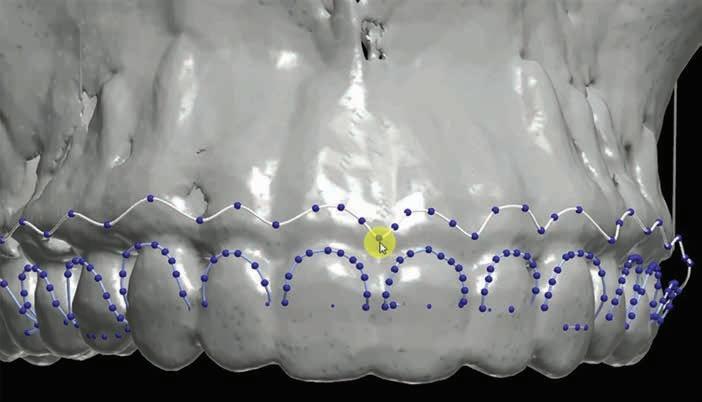

The use of a digital workflow to treat patients with APE has been proposed in situations with restorative treatments, as well as when no restorative treatment is anticipated.38,39 In this method, a CBCT scan is acquired to analyze the level of the alveolar bone crest in relation to the CEJ. An intraoral scan is acquired to aid in fabricating a surgical guide. Digital Imaging and Communications in Medicine files obtained from the CBCT are converted to Standard Tessellation Language format and then superimposed with Standard Tessellation Language files acquired from the intraoral scan. The level of the CEJ is then marked (Figure 5) to guide the gingivectomy incision line, followed by a second line 3 mm apical to the CEJ line to guide the bone resection.

TessellationLanguageformatandthensuperim posedwithStandardTessellationLanguage fi les acquiredfromtheintraoralscan.TheleveloftheCEJisthenmarked(Figure5 )toguidethe gingivectomyincisionline,followedbyasecondline3mmapicaltotheCEJlinetoguidethe boneresection.

Figure 5. After superimposition of the cone-beam computed tomographic scan and intraoral scan, the cementoenamel junction and future bone level are marked. Reproduced from Alhumaidan A, Alqahtani A, al-Qarni F. 3D-printed surgical guide for crown lengthening based on cone beam computed tomography measurements: a clinical report with 6 months follow up. Appl. Sci. 2020;10(16):5697, CC-BY 4.0. https://doi. org/10.3390/app10165697.39

Figures 5-7 are reprinted with approval from the authors.